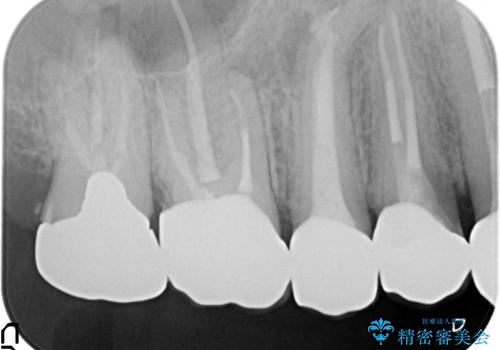

- 歯がない左側でものが咬めず、右側で咬むと歯が痛むので診て欲しいといらっしゃった方の症例です。

根尖病変が認められる歯は再根管治療を行い、歯根が破折していた左上4は抜歯しました。

インプラントは希望されなかったため、左側は1番から7番のロングスパンブリッジによる補綴を行いました。

今回用いたオールセラミッククラウンは、ジルコニアフレームという白い素材の上にセラミックを盛っているため審美性が非常に高いのが特徴です。

またジルコニアは人工ダイヤモンドの材料にも使われているほど高い強度を持っており、そのためオールセラミッククラウンは審美性だけでなく、奥歯やブリッジの補綴も可能とするクラウンです。